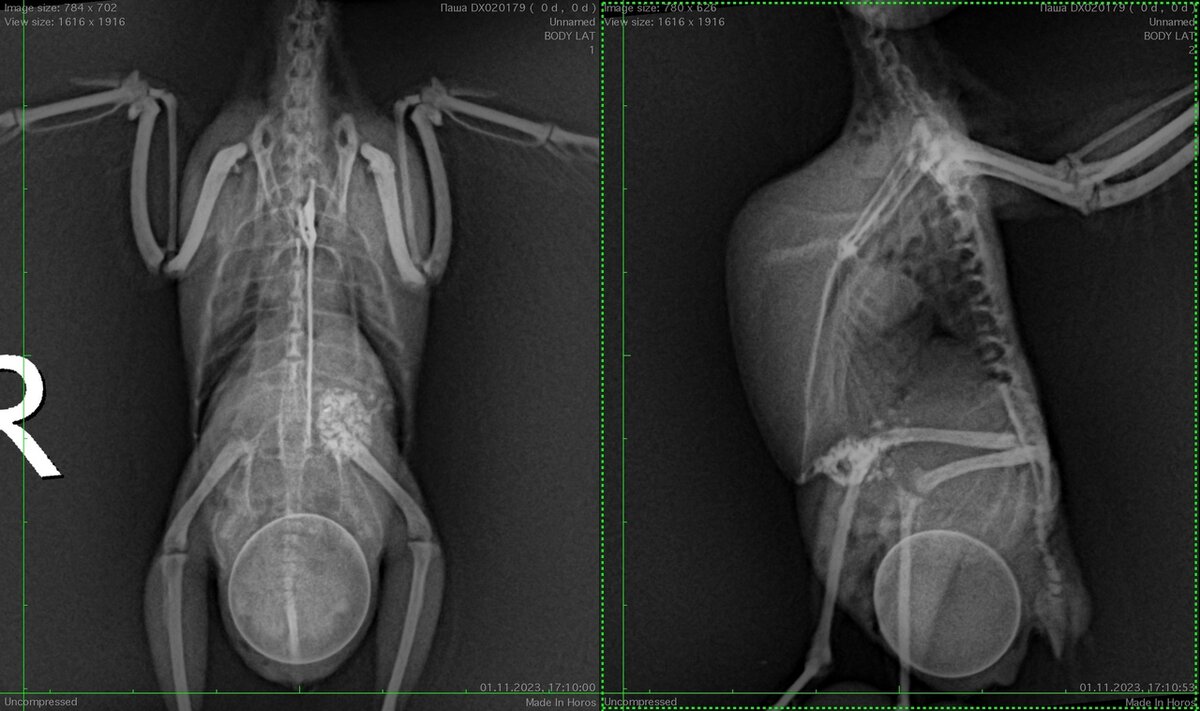

Вот свежий пример из моей практики. Волнистый попугай, который много лет считался самцом, плохо себя почувствовал (птица стала вялой, помёт стал скапливаться в области клоаки, живот увеличился).

Рентген подтвердил предварительный диагноз - дистоция. Но рентген показал и всё то, о чем написано выше, у птицы хроническая инфекция, и … серьёзные проблемы вообще со всем тем, что есть у птицы внутри.

Рентген волнистого попугая с дистоцией.